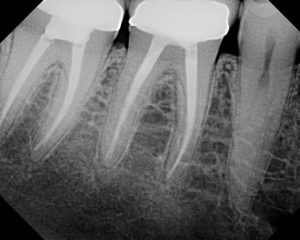

– X-rays

Endodontists may use x-rays during the procedure to check on the

status of the tooth. With the advancement of technology, there are now digital x-rays that produce less radiation, and they are developed immediately hence reducing the time you will spend in the dental chair.